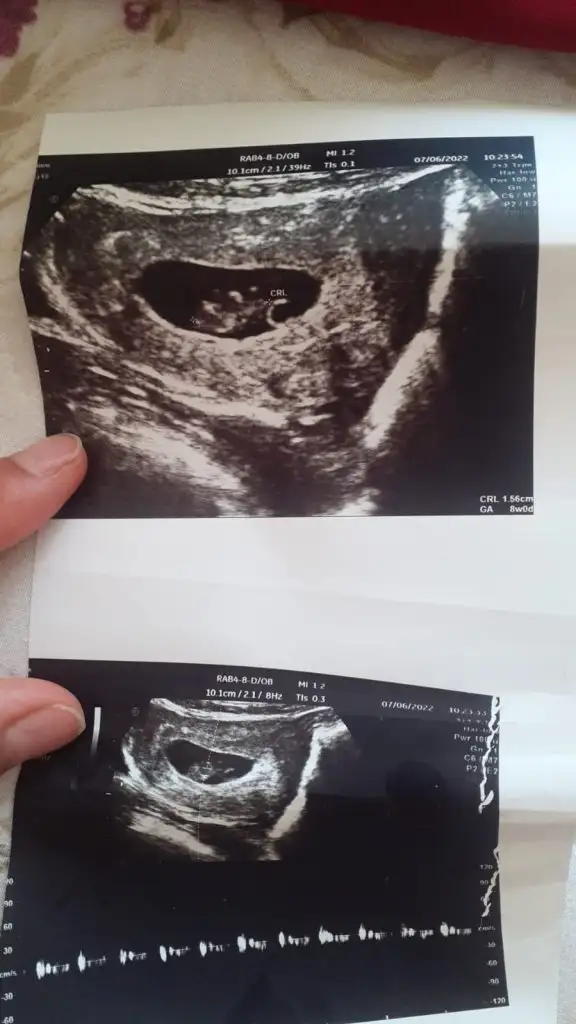

Baya küçükmüş canım benim ilk hamileliğimdeki 9 haftalık ultrasonum böyle :) erkek gibi hissettim ama sanki de sen öğrenmişsindir ama ne cinsiyeti kız mı? :)

Doktor birtürlü emin olamıyor ya nasıl iş anlamadım erkek testisi göremiom dedi kıza benzio ama emin değilim dio kızdır herlde ya